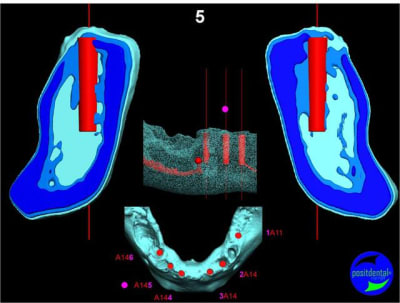

en attendant la pano voici les coupes de la S.I.A.O.

Image33_nwzawb.jpg

Image34_ixvkww.jpg

Image35_orinjf.jpg

Image39_nacsid.jpg

Image40_hkzycw.jpg

Image41_egzryy.jpg

Image42_p57obk.jpg

Image43_jgylho.jpg

Image44_ysqyf8.jpg

Image45_d112br.jpg

Image46_u9eg6l.jpg

Image47_yffnwq.jpg

Image48_ptc9lw.jpg

Image30_exkkml.jpg

Image31_p13zyn.jpg

Image32_ffzd3q.jpg

Image36_jfzwrz.jpg

Image37_inavxh.jpg

Image38_jfa54w.jpg